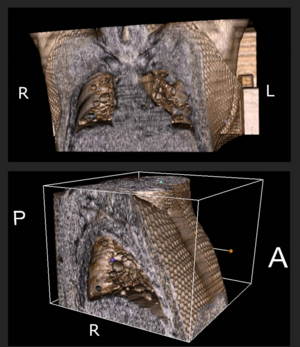

- 3.16 Two-Center Prospective, Randomized, Clinical, and Radiographic Study Comparing Osteotome Sinus Floor Elevation with or without Bone Graft and Simultaneous Implant Placement